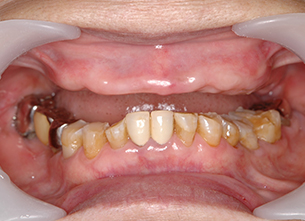

症例1 : 上下顎無菌顎症例

69歳、男性。

• 上顎は両側サイナスリフトと同時に即時荷重を行った。

• 下顎は抜歯即時埋入即時荷重を行った。

• 最終補綴物は、チタンのP.I.B.とM.B.のコンビネーションで修復した。

• 本症例の要旨は第39回日本口腔インプラント学会(大阪)にて症例報告した。